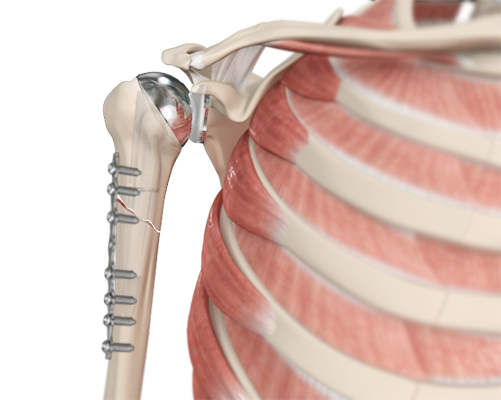

ORIF Proximal Humerus Fracture

Open reduction and internal fixation (ORIF) is a surgical technique employed for the treatment of fractures to restore the normal anatomy of the bone.

Periprosthetic Shoulder Fracture Fixation

Periprosthetic shoulder fracture fixation is a surgical procedure used to stabilize and repair a fracture that occurs around a shoulder prosthesis (such as after a total shoulder replacement or reverse total shoulder replacement).